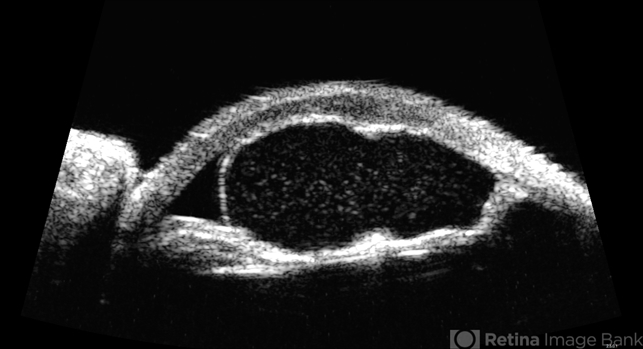

- cyst, iris, anterior chamber, immersion ultrasound

- UBM of recurring idiopathic iris cyst in 72 year old female